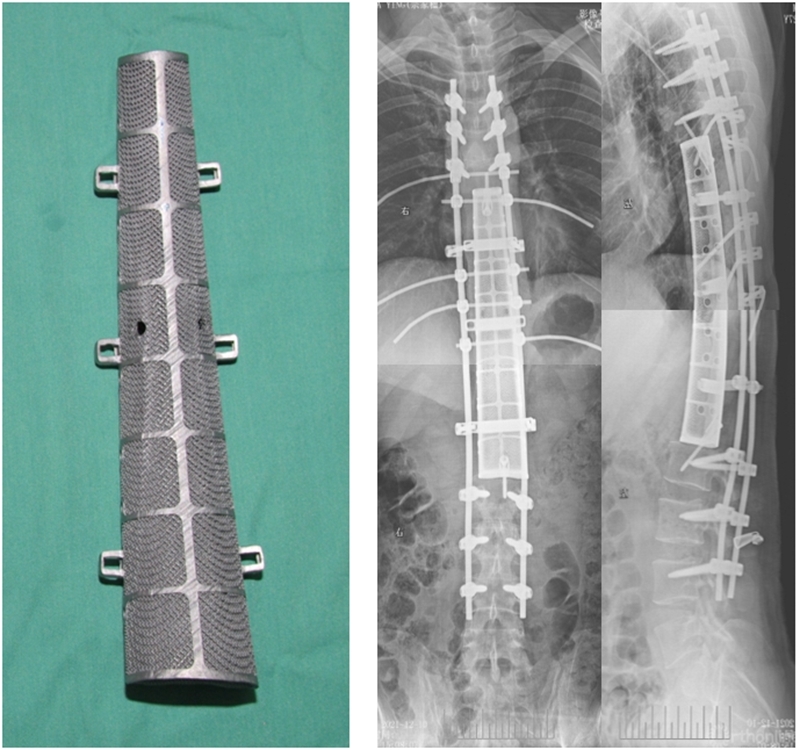

3D打印人工椎体精准植入

世界首例

2021年底空军军医大学唐都医院收治了一位特殊的病人,恶性纤维肉瘤侵蚀了患者的七节椎体,在背部形成破溃,并且造成了截瘫,整块切除的难度和危险性很大,切除后的重建也极具挑战性。术前团队与全院多个科室反复推敲模拟手术过程,制定手术方案。为了重建脊柱缺损,团队决定采用3D打印技术为患者量身定制钛合金人工椎体,确保脊柱稳定性。术中骨科、整形外科、胸外科,烧伤科、麻醉科等专家通力协作,手术全程18个小时,术后患者恢复良好。经过科技查新,这是世界首例脊柱七椎体肿瘤整块切除重建案例。回顾全程,团队完成了一场考验经验丰富度、协作默契度、工作认真度的实践大考,也着实打赢了一场酣畅淋漓的硬仗。